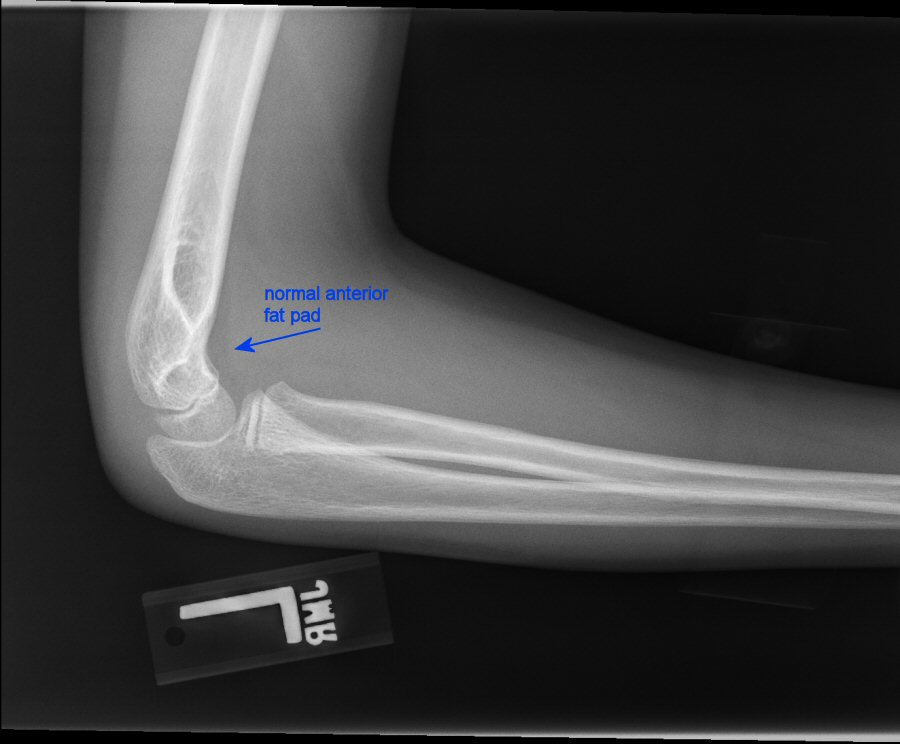

What is the most likely site of elbow fracture in pediatric patients?

Supracondylar

Unfortunately, they also tend to be hard to see on films. We often have to rely on elevation of the fat pads on plain films.

Where should you see a fat pad in a healthy elbow joint?